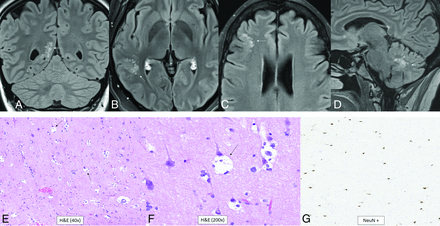

Diffuse pediatric-type high-grade glioma, H3 wild-type and IDH wild-type. MR images demonstrate diffusely infiltrating masses in the bilateral temporal lobes with mild mass effect, T2-FLAIR (A) and T2-hyperintensity (B, anterior arrows), and no enhancement (C). There is additional T2-FLAIR and T2-hyperintensity in the dorsal pons and posterior fossa leptomeningeal enhancement (posterior arrows). Histology reveals a high-grade diffusely infiltrating astrocytoma with high mitotic activity (D). The tumor shows ATRX retention (E) and wild-type IDH status (F) on immunohistochemical stains. Whole-genome methylation analysis showed a match to diffuse pediatric-type high-grade glioma. The tumor was H3 wild-type and IDH wild-type and had a TERT promoter mutation, which was identified on the neuro-oncology targeted next-generation sequencing panel.

Diffuse pediatric-type high-grade glioma is another of the 4 pediatric high-grade glioma types. It does not have an assigned WHO grade or a single defining molecular or genetic feature.1 About half of tumors previously classified as “pediatric glioblastoma” demonstrate mutations of histone 3 or uncommonly IDH1/2. The remaining heterogeneous tumors now fall under this new classification. The 3 recognized subtypes are characterized by MYCN, PDGFRA, and EGFR amplifications with numerous coexisting genetic abnormalities described.24 The MYCN subtype has high cellularity and mitosis, spindle, and epithelioid cell components; necrosis; and microvascular proliferation.25,26 The median age at diagnosis is 8–11 years (range, 2–18 years).24 There is no sex predilection overall, but there is a slight male predominance for the EGFR subtype (male/female ratio, 1.6:1).24 The location is usually supratentorial, with the posterior fossa approaching 20% of cases, depending on subtype.24 The MYCN subtype classically shows a solid, enhancing, diffusion-restricting, well-marginated temporal lobe mass abutting the meninges with tumoral necrosis, rare hemorrhage, and no calcifications.25,26 A tumor in the pons has greater enhancement and diffusion restriction compared with a diffuse midline glioma, H3 K27-altered.25 Figure 5 demonstrates a less-typical case without enhancement of the primary tumors.